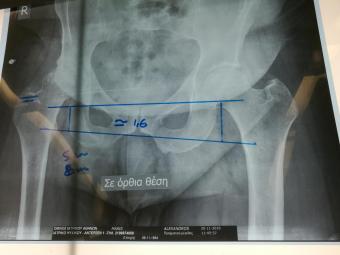

Стажування в приватній клініці у професора Христодулоса Афіни Греція листопад 2019

Компанія Lima надала стажування в ортопедичній приватній клініці місті Афіни Греція в листопаді 2019 року. Ендопротезування кульшового суглоба протезами компанії Lima малоінвазивним передньо-латеральний доступом у професора Христодулоса.